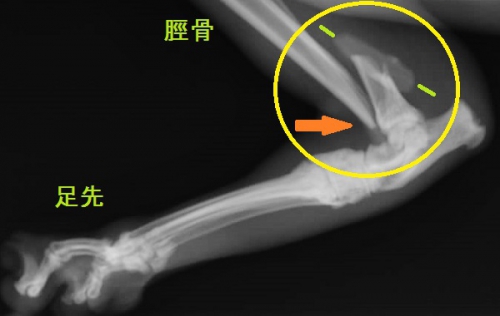

身体検査では全身がかなり痛い様子で、猫ちゃんは触ろうとすると威嚇してきます。その原因はすぐに分かりました。右側の脛骨遠位端(スネの骨の先端)の骨折があり、後ろ足を動かそうとすると足先が90度くらい内側外側へと自由自在に向いてしまい、ぶらぶらと力なく引きずられています。

よく見ると、骨折した骨の端が鋭利な刃物のようになって、皮膚の内側から皮膚を突き破っているではありませんか。(下写真でオレンジ矢印の先端が尖っている骨)

レントゲン検査では脛骨骨折と同時に上腕骨骨折が確認されました。脛骨の骨折部分には写真では見えにくいですが3つの骨折面があり、大小2つの骨片(骨の破片:緑マーカーの間)を伴って割れています。こういった骨が砕けたような骨折を分類上、粉砕骨折と呼びます。この例ではさらに骨折端(オレンジ矢印)が皮膚を突き破って一部外に出ていますので、複雑骨折(開放骨折)の状態です。